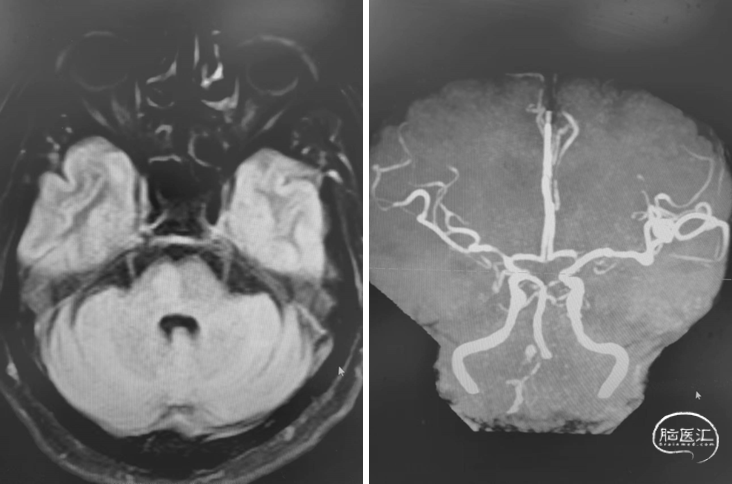

首次DSA 2022.4.9:

重要影像结论DSA:左侧椎动脉闭塞,右侧椎动脉V4段重度狭窄。

内科治疗后仍有新发梗死(2022.8.8):

重要影像结论:桥脑新发亚急性梗死灶,右侧椎动脉重度狭窄。